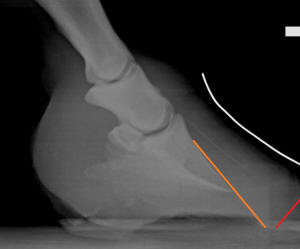

Figure 3

Eventually, this is

the goal: [Figure 3] to grow in a normal wall/lamellar

connection around the existing P3 (dashed line). There will, of

course, need to be very careful heel work done and probably

sweeping nutritional changes needed to achieve this, but keeping

the breakover trimmed correctly along the way is a big part of

success with these cases.

Important note: In a

rotated or severely flared hoof, do not trim the dorsal wall to

the dotted line in Figure 3 – wait for the new well-connected

growth. Instead, top dress the dorsal wall similar to the purple

line in Figure 2. In order for the generally weaker lamellar

wedge material to protect the dermis as well as a healthy hoof

wall would, it needs to be about twice the thickness of normal

hoof wall. Trimming the lamellar wedge down to normal wall

thickness (1/2”-5/8” or 12-15mm) overexposes the dermis to

damage.